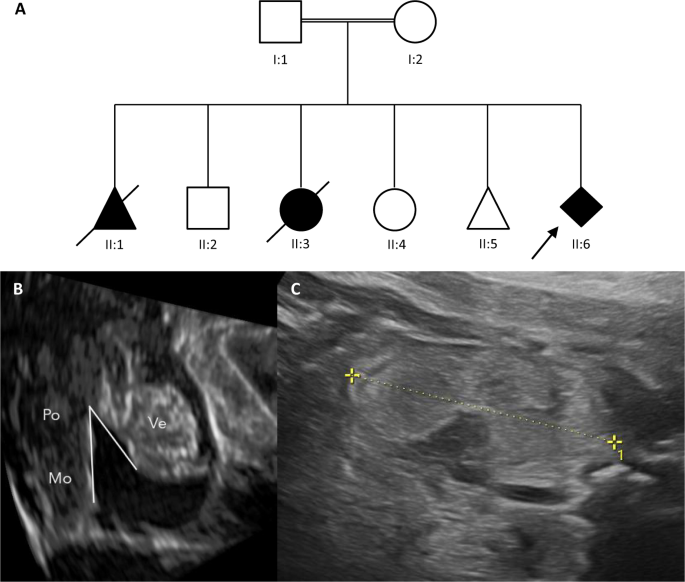

A fetus of consanguineous parents showed cerebellar vermis hypoplasia, enlarged hyperechogenic kidneys, oligohydramnios, and lung hypoplasia in the 24th week of pregnancy. One previous pregnancy of the same couple was terminated because of a similar severe phenotype and in another pregnancy, with anhydramnios a girl was born in the 25th week with Dandy-Walker malformation and encephalocele, who died shortly afterward. Furthermore, the couple had one abortion and has two healthy children. For the current pregnancy, a trio whole-exome analysis was performed, and homozygous deletion of exons 3–5 in EXOC3L2 was detected by CNV analysis. The parents were both heterozygous carriers of this deletion (case 22 in Table 1 and Fig. 3).

Both parents (I:1 and I:2) carry a heterozygous deletion of exons 3, 4, and 5 in EXOC3L2, which has been detected in the fetus from the last pregnancy (II:6) in a homozygous state (A). A male fetus in the first pregnancy (II:1) showed renal dysgenesis. The pregnancy has been interrupted in the 22nd gestational week. A healthy boy has been born from the 2nd pregnancy (II:2). In the 3rd pregnancy, an anhydramnios has developed and a girl has been born spontaneously in the 25th gestational week with a Dandy-Walker malformation and an encephalocele, who died shortly after the birth (II: 3). From the 4th pregnancy, a healthy girl has been born in the 39th gestational week (II:4). The 5th pregnancy ended in an abortion in the 15th gestational week (II:5). The fetus of the last pregnancy (II:6, index case) with a homozygous deletion in EXOC3L2 showed in the 30 + 5 gestational week lung hypoplasia, hypoplastic vermis cerebelli (B: Ve – Vermis, Po – Pons, Mo – Medulla oblongata; cc 15,8 mm (<5. perc), ap 11,4 mm (25. perc.), brainstem-vermis angle: 38,2°) and hyperechogenic, enlarged kidneys (C).